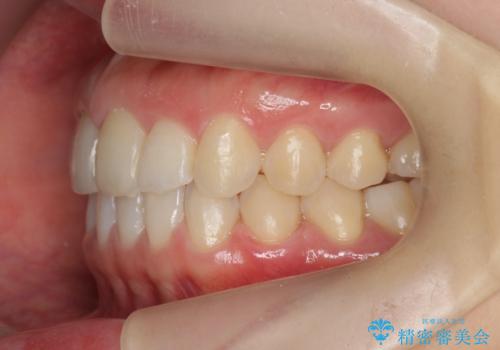

出っ歯に見える前歯の改善 部分ワイヤーとマウスピース矯正

- 出っ歯に見える前歯の改善を希望され、来院されました。

マウスピースでは改善の難しい歯の動きを部分ワイヤー矯正で整えたのち、奥歯の噛み合わせや細かい歯の並びをマウスピース矯正インビザラインで整えていきます。

最終的な前歯の並びに大変満足いただくことができました。